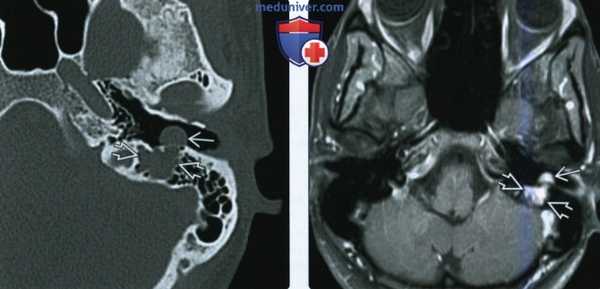

(Слева) При аксиальной КТ в костном окне у пациента с полипом в наружном слуховом канале определяется опухоль неправильной формы, расположенная в области сосцевидного сегмента ЧН VII.

(Справа) При аксиальной MPT Т1 ВИ С+ FS у этого же пациента определяется контрастирующаяся ШЛН в сосцевидном сегменте ЧН VII, выбухающая через костный дефект в НСК.